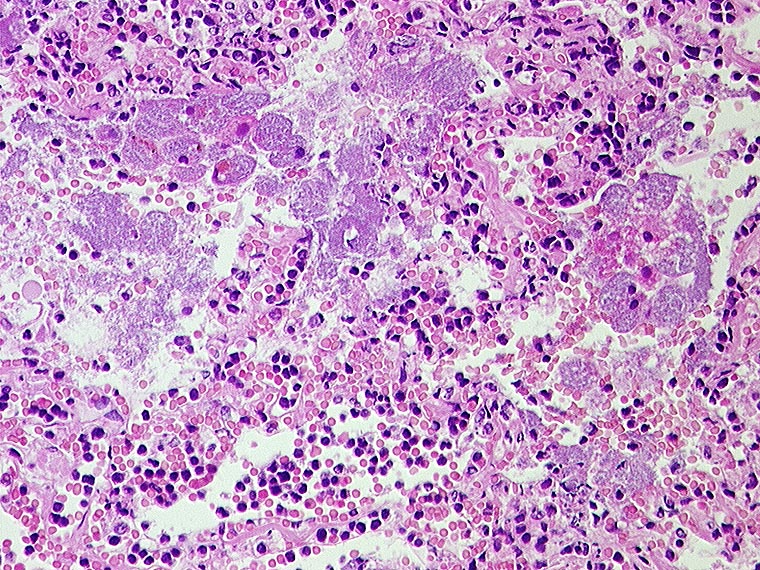

Infarktoide areaktive Pneumonie bei Lymphom

Intraalveoläre Blutungen und Bakterienrasen sowie zahlreiche Makrophagen gefüllt mit Bakterien. Die zytoplasmaarmen kleinen Zellen entsprechen Lymphominfiltraten. Ein granulozytäres Entzündungsinfiltrat fehlt.

T-Zell Lymphom mit leukämischer Ausschwemmung.

Lymphom seit 3 Jahren. Massive Leukozytose.